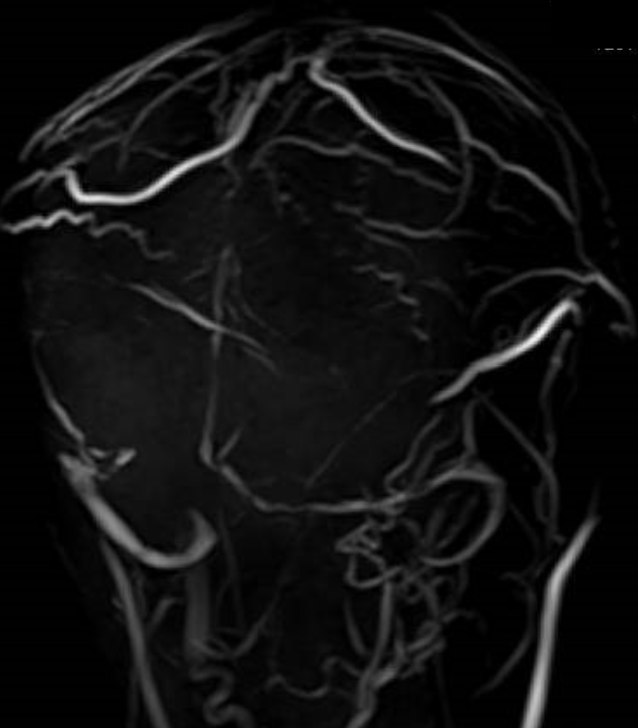

症状は頭痛、めまい、嘔吐、巣症状(麻痺やしびれ)、意識障害など症状は多岐にわたり非特異的ですが、頭痛は最多の症状であり、頭痛疾患においては必ず除外しないといけない疾患の1つです。頭部MRI検査では、この静脈洞を観察する方法(MRV)や通常のMRI画像にて静脈洞に血栓形成の所見があるかなどを確認することが出来るため、診断は比較的容易です。治療法は、抗血栓薬の使用と原疾患への対応が必要です。予後に関して、以前は死亡率が30~50%と報告もありましたが、近年は早期発見・適切な早期治療介入により神経学的後遺症なく70~80%の方が回復します。そのため、診断は確実にする必要がありますが、この疾患の診断にはMRI検査と専門的な知識と経験が不可欠です。

可逆性脳血管攣縮症(Reversible Cerebral Vasoconstriction Syndrome:RCVS)は、急性発症する激しい頭痛を主症状とする疾患です。この頭痛は「雷鳴様頭痛」と形容され、突然発症し、1分未満で痛みの強さがピークに達するものと定義されます。さらに、頭部画像検査では、多発性かつ分節状の脳血管攣縮が可逆的に認められることが特徴です。

画像では、同時にくも膜下出血や脳出血・脳梗塞・脳浮腫を合併することがあります。MRI画像での分節様の血管攣縮は、頭痛発症から2~3週間後がピークとなり診断が可能となります。頭部MRIにて確認できる多発性分節性可逆性脳血管攣縮は、3か月以内に改善すると言われています。

椎骨動脈解離

動脈は内膜、中膜、外膜と3層構造になっていますが、外傷や高血圧などなんらかの原因で、脳血管(脳動脈)の内膜層が剥がれてしまいそこに血流が入り込む事で、血管膨れて動脈瘤を形成し、脳出血やくも膜下出血を起こしたり、血管が閉塞して脳梗塞を引き起こしてしまう病気です。若年〜中年者の方に多く見られ、危険因子は高血圧、喫煙習慣などが挙げられます。日本人では、脳幹や小脳に灌流する椎骨動脈という重要な血管に起こる事が圧倒的に多いです。椎骨動脈解離は、後頭部に起きる突然の強い頭痛で発症します。この病気の怖い点は、くも膜下出血や脳梗塞を起こしていなくても椎骨動脈が解離する事による血管痛のみで強い頭痛を自覚します。そのため、神経症状を合併してない頭痛のみの時は、CT検査で脳卒中を否定しても、MRIなどで脳血管の評価をしなければ見落としてしまう可能性があります。治療法は入院をしてカテーテルや開頭手術になりますが、頭痛のみの症状でくも膜下出血や脳梗塞を起こしていなければ、血圧管理のみで経過を見ることがありますが、頻回なMRI検査による解離血管に変化がないか確認する必要があります。診断、治療が遅れると生命の危機に直面する非常に怖い病気の1つです。